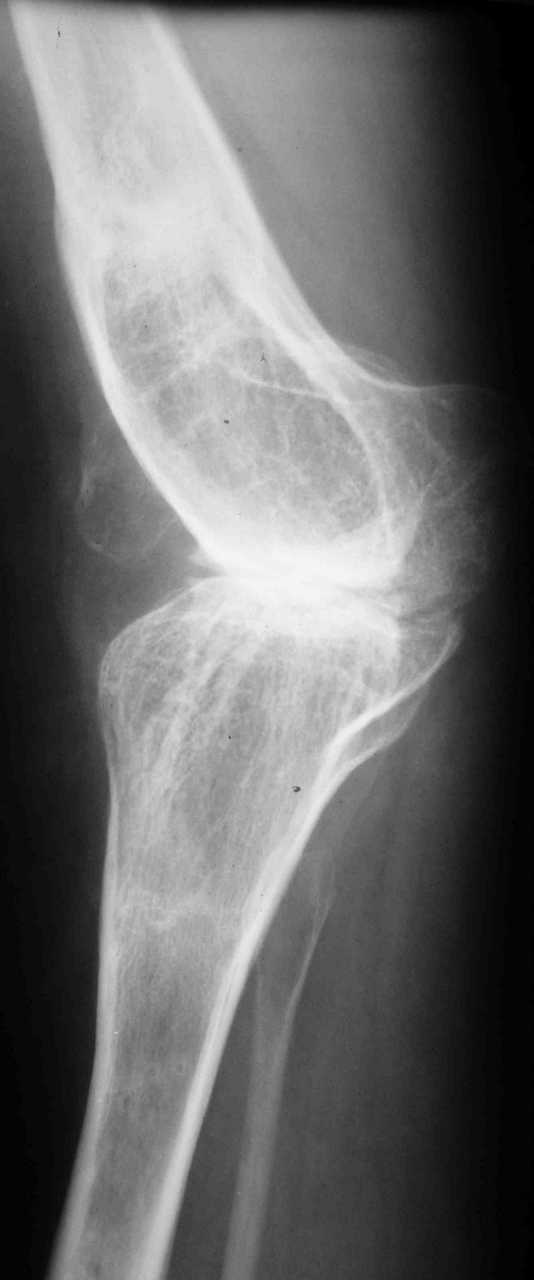

В настоящее время нет возможности сделать осевые снимки всей конечности. Это всё чем я раполагаю на сегодняшний день.

Спасибо. Картина несколько прояснилась. А планов в отношении тазобедренного сустава нет? Или пациентку беспокоит только колено.

Пациентку беспокоит только выраженный болевой синдром в коленном суставе.